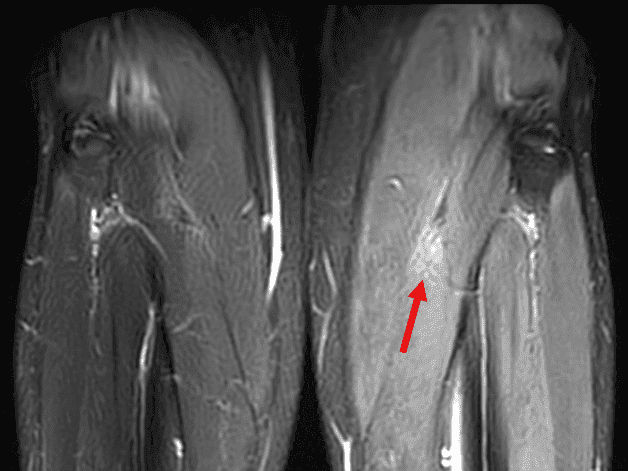

Les anomalies de signal sont également visibles dans le plan coronal, écartant l'hypothèse d'une origine artéfactuelle.

Coronal T2 FS